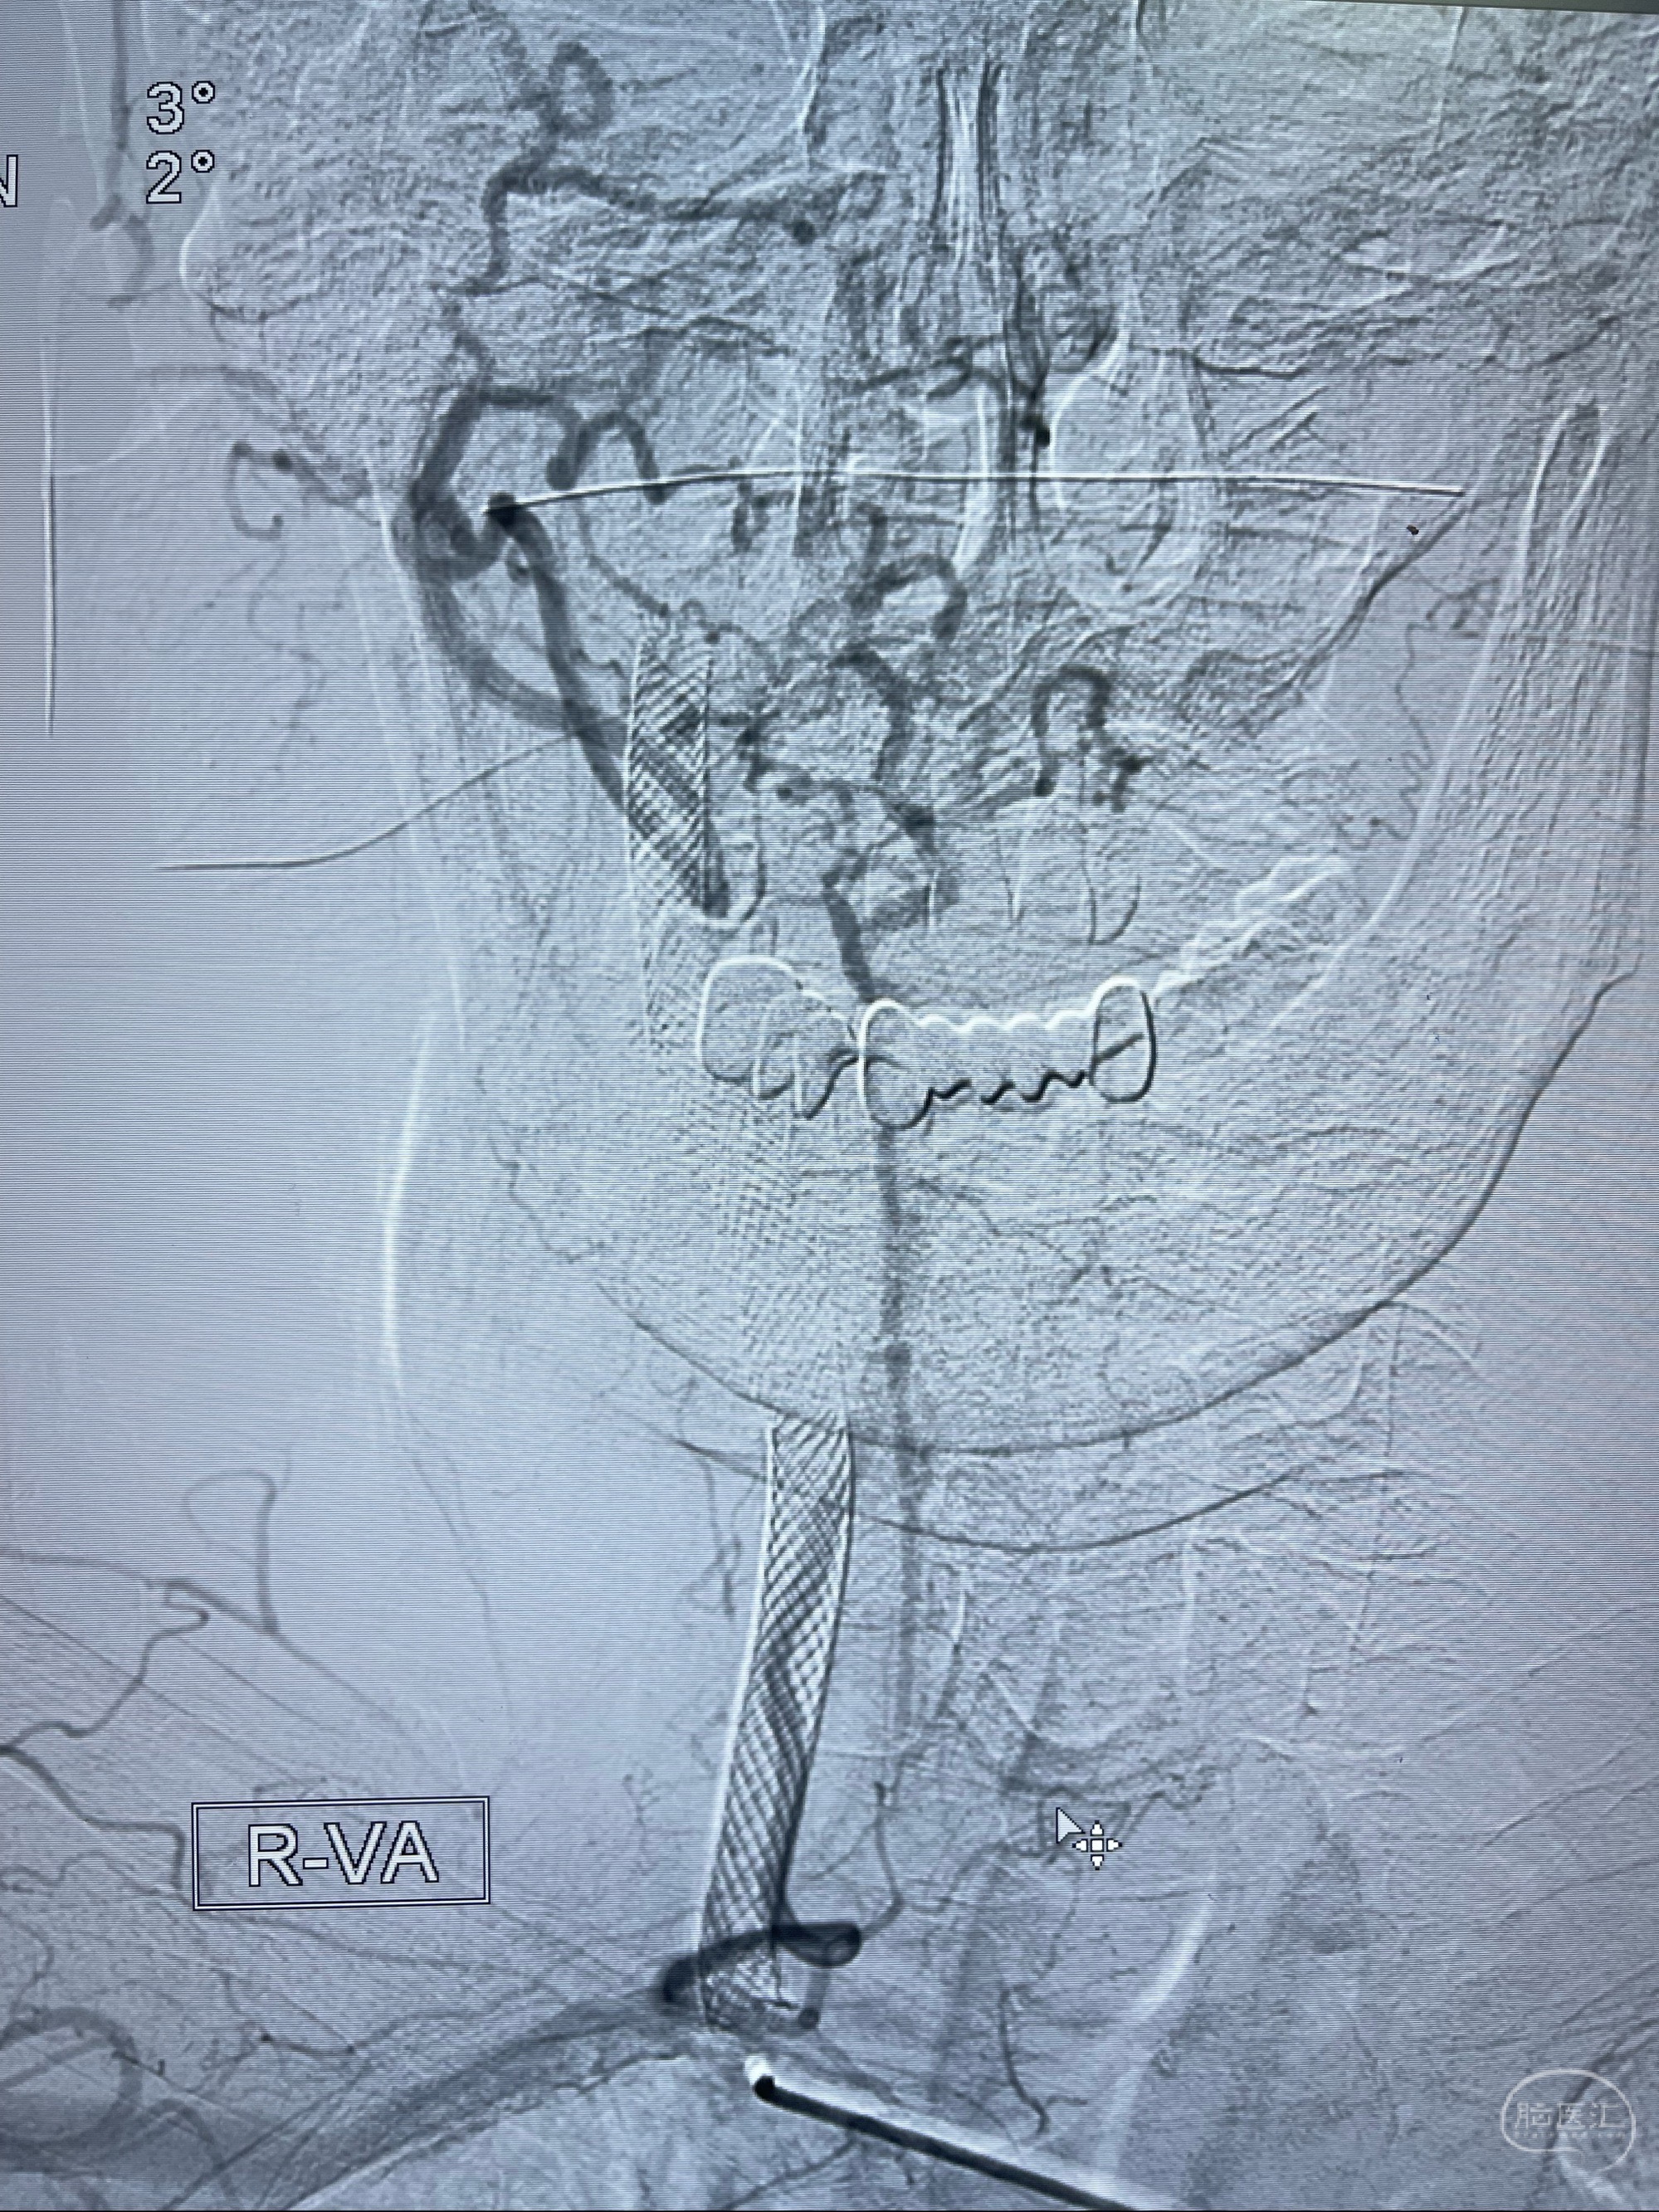

双抗准备后于2023-07-13在全麻下行右侧颈内动脉功能保护

088NeuroMAX100cm长鞘在125cmMPA及黑泥鳅导丝引导下超选择性插入右侧颈内动脉支架内

经导引导管造影显示支架远端颈内动脉不规则狭窄伴局部充盈缺损,同时行全身肝素化5ml

路径图下4-20mm球囊在导丝引导下超选择性至狭窄段,以6-8个大气压扩张,持续30s

泄除球囊造影显示局部管腔扩张佳

后移球囊至颈段狭窄段,以8-12个大气压扩张,持续30s后泄除球囊

即刻造影显示狭窄扩张佳

重新行“路径图”,支架导管在微导丝引导下超选择性插入至右侧颈内动脉眼段,4.5-50mmLeo支架释放,远心端位于海绵窦段,近心端位于岩骨段狭窄段以近

即刻造影显示支架贴壁佳

路径图下,5.5-50mmLeo支架导管在微导丝引导下超选择性插入远段Leo支架内

两枚支架部分重叠

多次确认支架位置及打开贴壁情况

支架完全打开,近心端位于原颈动脉支架远心端内